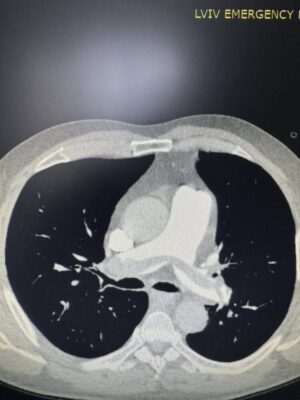

“Вчора ввечері до нашої клініки потрапив чоловік із блискавичним розвитком тромбоемболії легеневої артерії — стану, який у багатьох випадках забирає життя за лічені хвилини. Другий – військовий, який лікувався в хірургічному відділенні з приводу мінно-вибухової травми та сьогодні отримав важку масивну тромбоемболію легеневої артерії”.

Команда фахівців вирішила провести малоінвазивну ендоваскулярну тромбаспірацію — процедуру, що дозволяє механічно видалити тромб із легеневої артерії без відкритої операції. Методика, яку лікарі нещодавно освоїли на конгресі інтервенційних радіологів у Барселоні, виконувалась під рентгенконтролем за допомогою катетера та спеціальної системи аспірації.